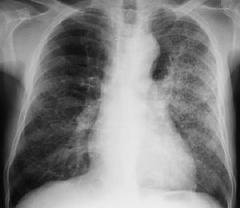

肺炎链球菌肺炎是由肺炎链球菌所引起的肺实质性炎症。通常起病急骤,以高热,寒战,咳嗽,血痰及胸痛为特征。在X片胸片中呈肺段或肺叶急性炎性实变。近年来因为抗菌药物的广泛应用,使本病的起病方式,症状以及X线改变均不典型。

3.X线检查 早期可见肺纹理加深或限局于一个节段的浅薄阴影,以后有大片阴影均匀而致密,占全肺叶或一个节段(图24-8),经治疗后逐渐消散。可见肺大泡。少数病例出现胸腔积液。值得指出,在肺部体征出现之前,即可能用X线透视查出实变。多数患儿在起病3~4周后X线阴影消失。